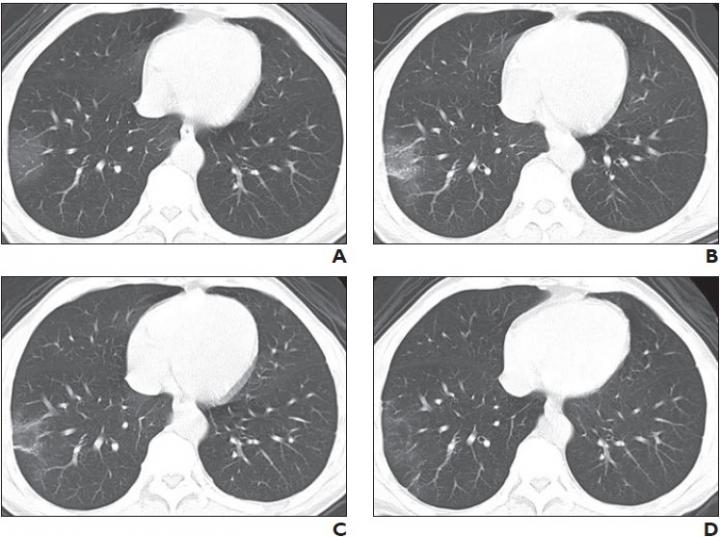

A, Initial chest CT image obtained 2 days after onset of symptoms shows small region of subpleural ground-glass opacities in right lower lobe, for CT score of 1.

B, Chest CT image obtained on day 3 of treatment shows slightly enlarged region of subpleural ground-glass opacities with partial crazy-paving pattern and consolidation, for CT score of 3.

C, Chest CT image obtained on day 5 of treatment shows partial resolution of consolidation, for CT score of 2.

D, Chest CT image obtained on day 14 of treatment shows continued resolution of consolidation with minimal residual ground-glass opacities, for CT score of 1.